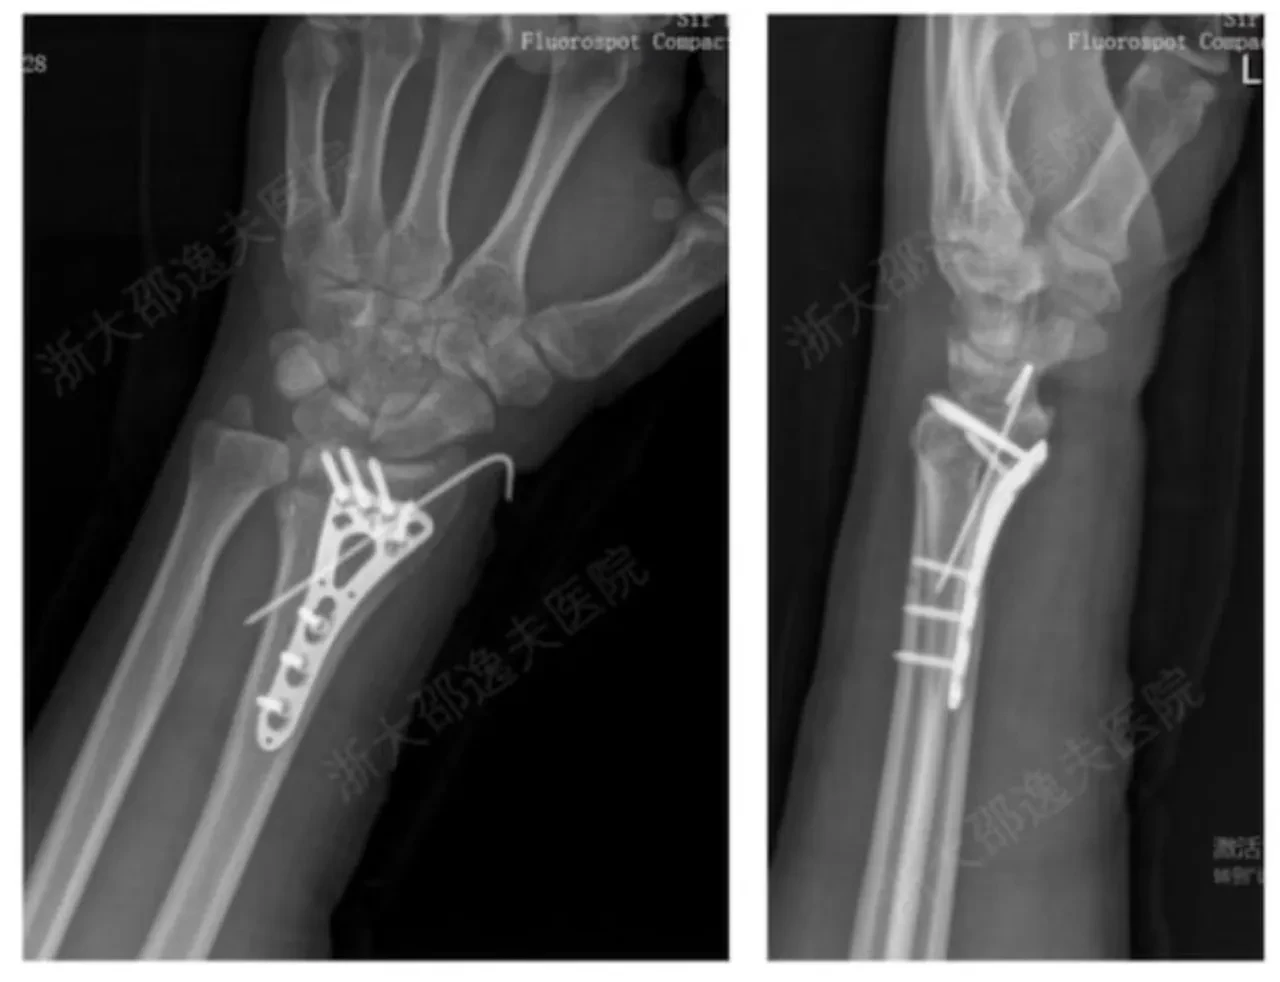

İlk klinik uygulamalarda, bilek kırığı yaşayan bir hastaya küçük bir kesiyle enjekte edilen yapıştırıcının, kırık parçaları 3 dakika içinde sabitlediği bildirildi. Araştırma ekibi, şimdiye dek 150’den fazla hastada yapılan testlerin başarılı geçtiğini ve herhangi bir komplikasyona rastlanmadığını açıkladı.

Yapıştırıcının maksimum yapışma gücü yaklaşık 180 kilogramı buluyor. Ayrıca, kesme ve basma dayanımı açısından da kemik dokuya benzer özellikler gösteriyor. Uzmanlar, bu tür bir teknolojinin ortopedi, travmatoloji ve spor hekimliği gibi alanlarda devrim yaratabileceğini belirtiyor.